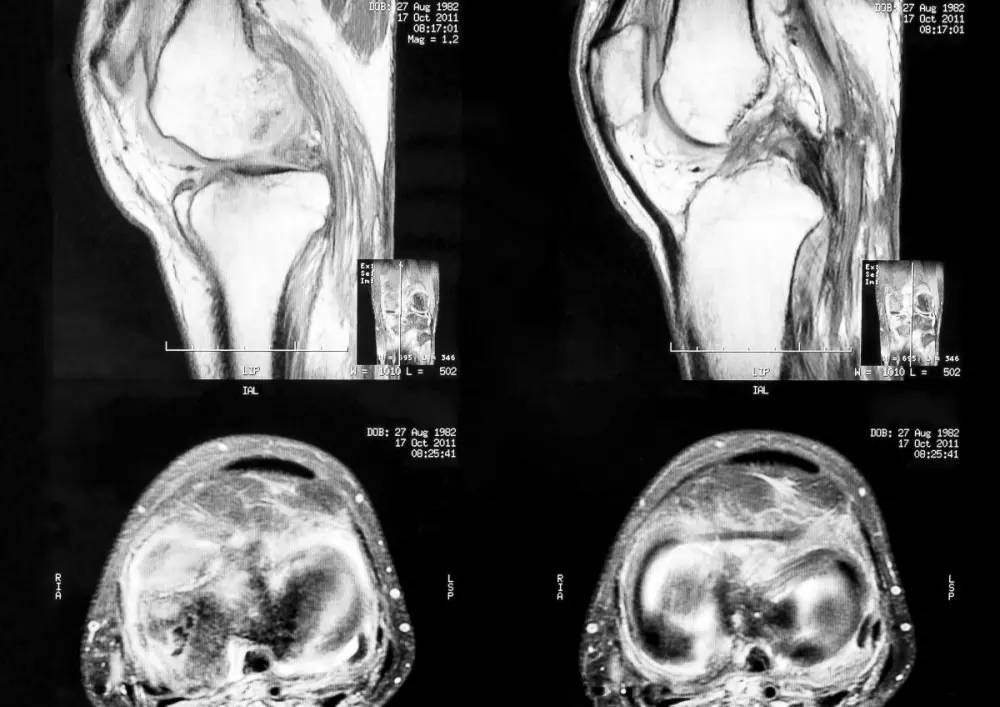

Chondromalacja rzepki

W dziale „Z praktyki gabinetu” znajdą Państwo artykuł pt. „Chondromalacja rzepki”. Nazywane są tak nieprawidłowości w obrębie chrząstki stawowej. Problem ten dotyczy głównie młodzieży i dorosłych, w szczególności kobiet. W tekście prezentujemy przykład 28-letniej pacjentki, która doznała urazu podczas jazdy na nartach, a u której stwierdzono chondromalację rzepki II/III stopnia z bocznym przyparciem bez objawów klinicznych. Prezentujemy opis fizjoterapii w takim wypadku.